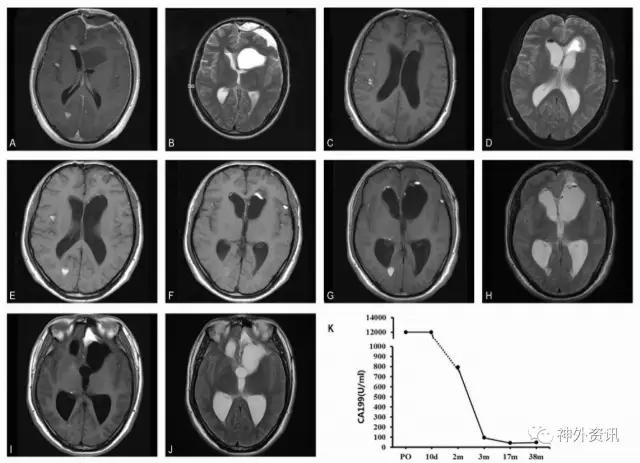

进一步追问病史,并完善胸腹部CT,以排除其他部位导致CA-199升高的常见癌性和非癌性疾病;相关检查均未见明显异常。该患者诊断考虑颅内囊性病变伴破裂。患者有明显颅高压症状,遂行开颅病变切除术。术中可见病变为囊性,内含黄色脂质样物质(图1F),吸除肿瘤内容物并予囊腔反复冲洗,囊肿包膜予近全切除。术后持续腰大池置管引流辅助廓清脑脊液内残余囊肿内容物。术后病理证实为颅内表皮样囊肿(图1G)。免疫组化显示CA-199染色强阳性(图1H),CA-125、CEA中等强度染色,CA-242阴性。术后复查MRI显示脂质样物质基本清除(图2A,B),术后第10天患者血清肿瘤标志物水平仍处于极高水平(图2K)。

患者术后2周顺利出院,未遗留神经系统功能缺失。密切随访患者磁共振并检测血清肿瘤标志物,术后2个月复查血清CEA、CA-125、CA-242已恢复至正常水平,CA-199也显著回落,并在此后的随访中呈持续下降。术后第38个月复查,CA-199出现了反弹(图2I-K),同期MRI复查提示残余病变增大。由于患者无明显症状,遂未对其进一步干预,继续随访观察。

图2. 患者随访资料。术后1个月磁共振(A,B)、术后2个月磁共振(C,D),术后1个月磁共振、术后半年磁共振(E,F)以及术后1年半磁共振(G,H)提示残余肿瘤逐渐缩小, CA-199同步下降。术后3年的磁共振(I,J)提示左侧颅底处肿瘤增大,CA-199水平也相应地从41.7U/ml 上升至47.0 U/ml。